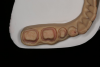

Fig 43. PMMA provisional digitally fabricated and milled.

Figure 43

Fig 44. Splinted PMMA seated.

Figure 44

Fig 45. Occlusal view of seated PMMA provisionals.

Figure 45